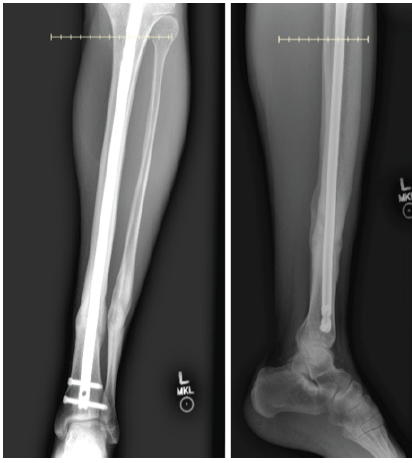

Six months after exchange nailing, the patient underwent open reduction and treatment of tibial pseudoarthrosis with augmentation of the non-union site using two pledgets of rhBMP-2 (Medtronic INFUSE™, total dose 4.2 mg) and iliac crest autograft. Intraoperatively, the pseudoarthrosis site was debrided and prepared before grafting. The intramedullary nail was retained for stability. Fig. 4 for post-operative imaging.

Figure 4: Radiographs demonstrate healing of the tibia and fibula after isolated tibial revision with debridement, hardware removal, bone morphogenetic protein application, and iliac crest bone grafting, without intervention at the fibular site.